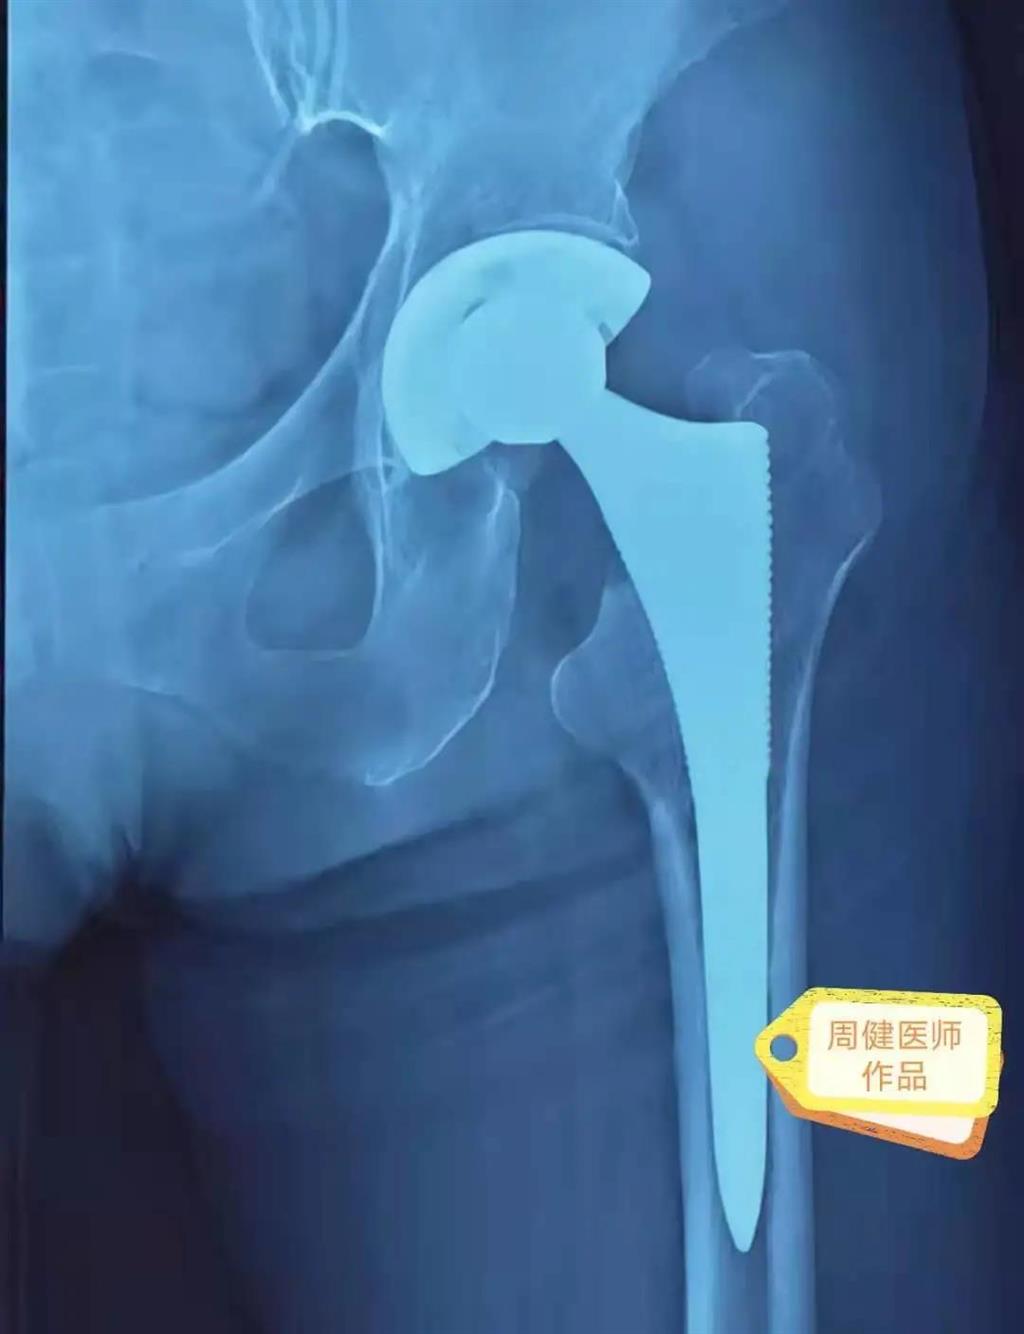

6月30日的“關(guān)節(jié)置換術(shù)”,患者是一位上了年紀的老人,苦于病痛折磨多年的他四處“求醫(yī)問藥”,最后在多位專家醫(yī)師及病友地力薦下選擇了和平國際醫(yī)院,在醫(yī)師團隊“偷天換日”般的手術(shù)后,老人成功告別了苦纏多年的病痛。

周健說,這場“關(guān)節(jié)置換術(shù)”對于他們團隊而言其實算是比較普通的手術(shù),因為做過很多同類的手術(shù),成功案例繁多,因此在手術(shù)操作上有較多地實操經(jīng)驗。“不過話雖如此,作為醫(yī)生我們對于每一場手術(shù)都會全力以赴,這是為醫(yī)者的職責也是義務(wù)。”